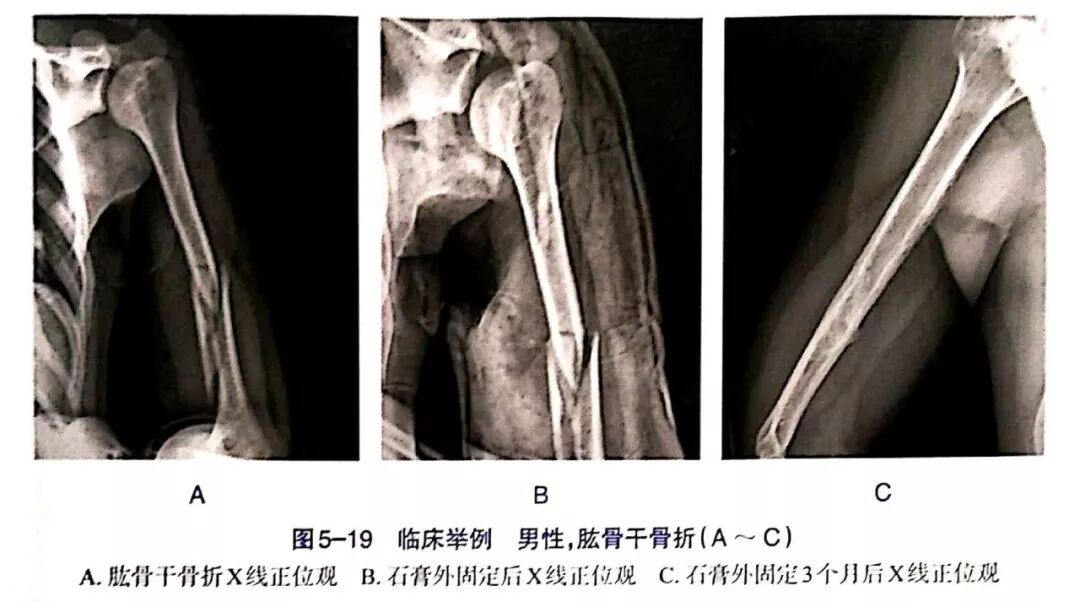

Clinical and Radiographic Imaging